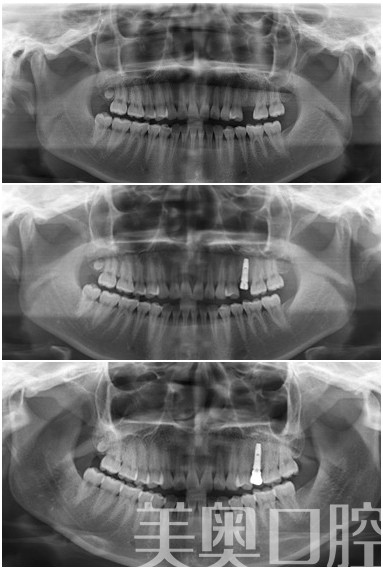

美奥(苏州)5S即刻种植牙

技术推荐:奥齿泰种植牙、瓷睿刻技术

美奥点评:奥齿泰种植牙是比较经济的一款种植牙系统,价格容易接受,但是瓷睿刻技术是一种即刻修复技术,造价比较昂贵,对于时间充裕的患者,可以选择普通的全瓷冠来修复。

扩展阅读:瑞士ITI种植牙、德国费亚丹种植牙、无菌手术室、瓷睿刻技术